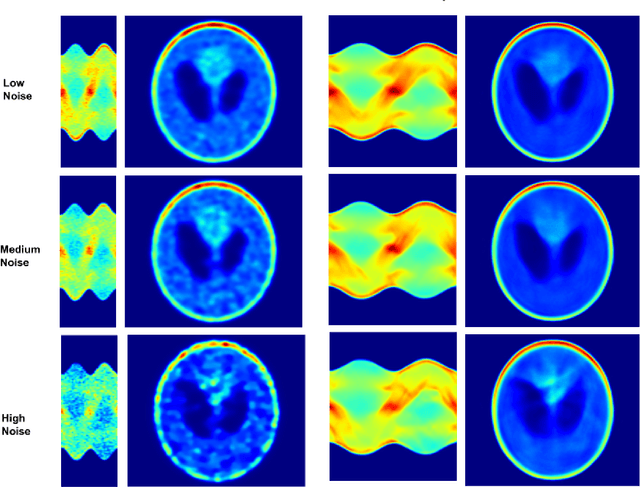

Abstract:A novel method for sinogram denoise based on Generative Adversarial Networks (GANs) in the field of SPECT imaging is presented. Projection data from software phantoms were used to train the proposed model. For evaluation of the efficacy of the method Shepp Logan based phantom, with various noise levels added where used. The resulting denoised sinograms are reconstructed using Ordered Subset Expectation Maximization (OSEM) and compared to the reconstructions of the original noised sinograms. As the results show, the proposed method significantly denoise the sinograms and significantly improves the reconstructions. Finally, to demonstrate the efficacy and capability of the proposed method results from real-world DAT-SPECT sinograms are presented.

Abstract:A novel method for SPECT angle interpolation based on deep learning methodologies is presented. Projection data from software phantoms were used to train the proposed model. For evaluation of the efficacy of the method, phantoms based on Shepp Logan, with various noise levels added were used, and the resulting interpolated sinograms are reconstructed using Ordered Subset Expectation Maximization (OSEM) and compared to the reconstructions of the original sinograms. The proposed method can quadruple the projections, and denoise the original sinogram, in the same process. As the results show, the proposed model significantly improves the reconstruction accuracy. Finally, to demonstrate the efficacy and capability of the proposed method results from real-world DAT-SPECT sinograms are presented.